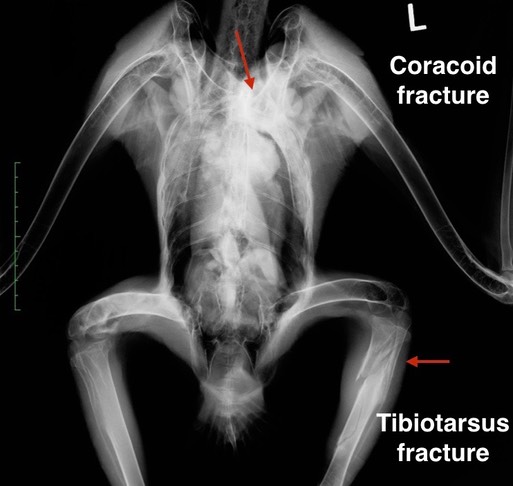

Bald Eagle 19-534

A young Bald Eagle was found along a highway near Wallowa, in far eastern Oregon. An exam revealed old fractures in the left coracoid and left tibiotarsus, likely the result of being hit by a car two or three weeks earlier. Both fractures were healed. It is doubtful that he will be fully flighted when completely recovered, but it seems like he deserves a chance after surviving such traumatic injuries.